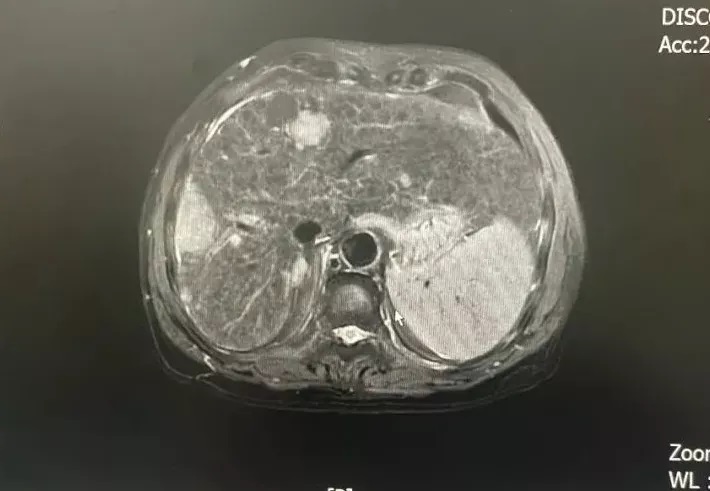

和平國際醫學影像中心是致力于疑難病診斷的專業醫療機構。作為精準影像的追尋者,深度健...